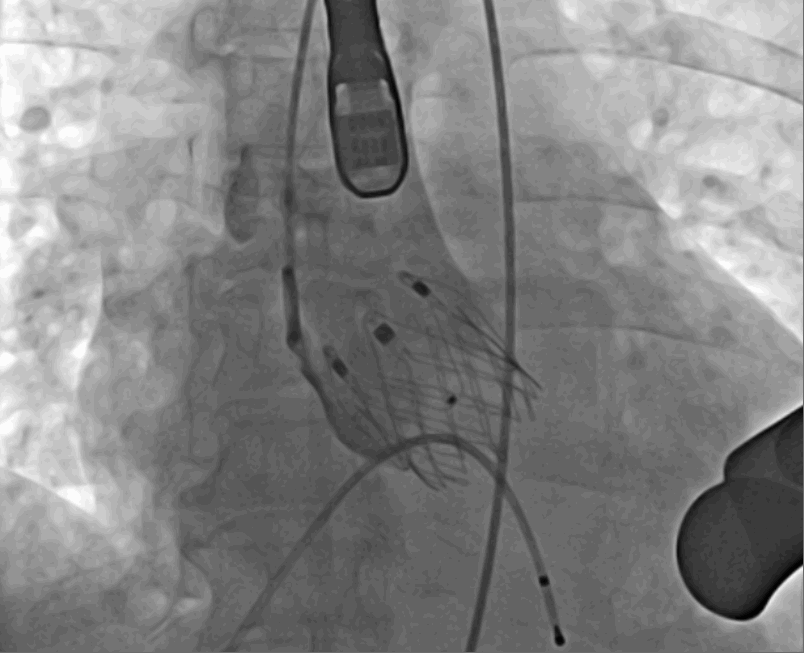

術(shù)前DSA影像圖

術(shù)中釋放定位鍵后DSA影像圖

術(shù)中瓣膜釋放過程

手術(shù)采用經(jīng)心尖入路,對患者進行全麻后,在左側(cè)心尖處做3-4cm微創(chuàng)手術(shù)切口,在DSA及超聲引導(dǎo)下手術(shù)順利完成。從導(dǎo)入器械到完成瓣膜置入,僅耗時約10分鐘。術(shù)后即刻主動脈瓣返流程度由術(shù)前大量返流轉(zhuǎn)為消失,患者于導(dǎo)管室拔除氣管插管,次日由ICU轉(zhuǎn)入普通病房。